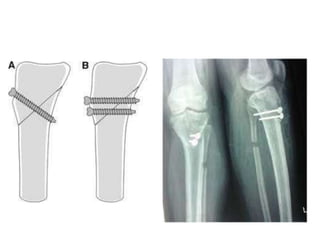

Lateral tibia and fibular

epiphysiodesis

indications

mild to moderate deformity with growth remaining

outcomes

up to 25% may require formal osteotomy due to residual

deformity

a. transient hemiepiphysiodesis

tether physis with 8-plates or staple

may remove implant once correction is achieved

simple

allows for gradual correction is children with adequate

growth remaining

b. permanent hemiepiphysiodesis

obliteration of physis through small, lateral incision

limited surgery

overcorrection is uncommon

cannot correct rotational deformity

up to 25% may require formal corrective osteotomy